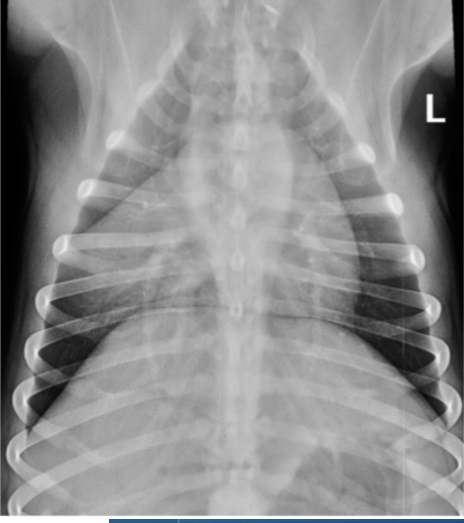

Q

We can see tramlines and donuts. Which lung pattern is shown here?

A

Interstitial

This is like looking through mist or a lace curtain; structures are not obliterated, but are greyed-out.

Donuts and tramlines = abnormal thickening of the airway (bronchiole) walls -> bronchial pattern